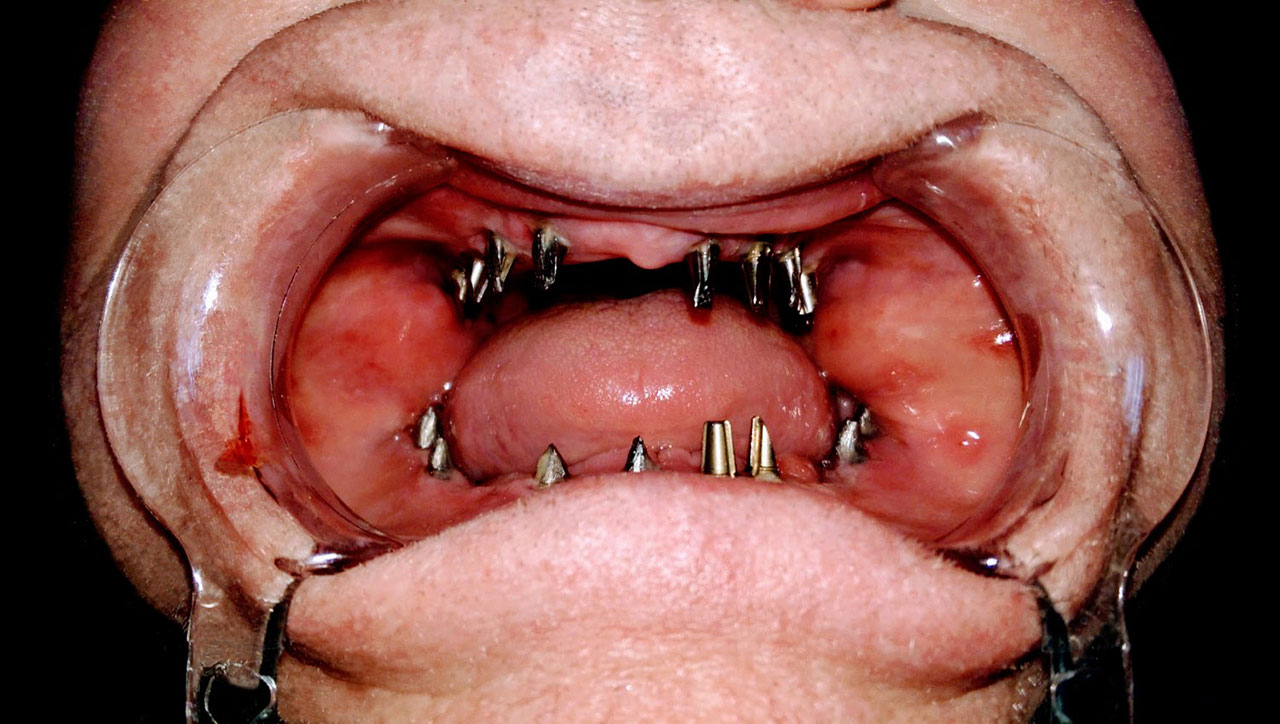

• esettanulmany-07

Teljes fogatlanság.

• esettanulmany-14

Alsó- felső fogatlan állcsont teljes implantációs helyreállítása.